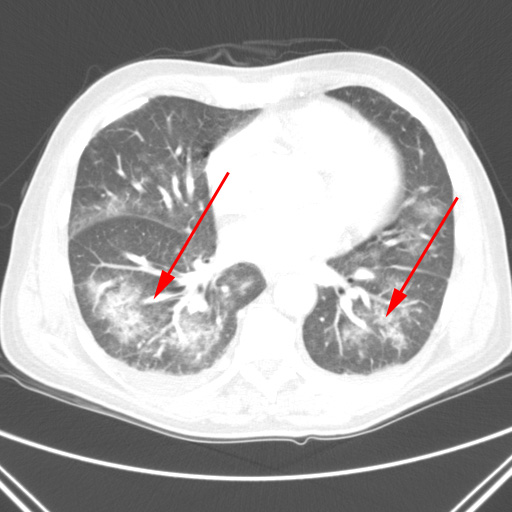

To CT-skanninger af lungerne på samme patient. Først er det øverste billede taget og 6 dage senere tages billedet neden for. Patienten udvikler lungebetændelse, som fremstår som hvide områder i lungerne på billedet neden for (røde pile).